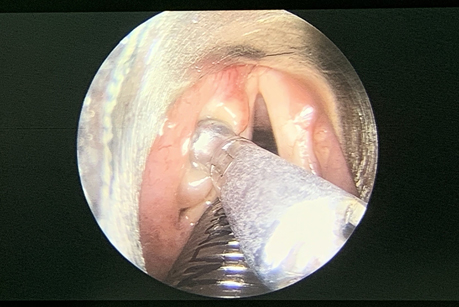

用喉钳钳取部分肿物,见脓性分泌物流出,喉钳牵拉肿物,喉剪切除囊肿